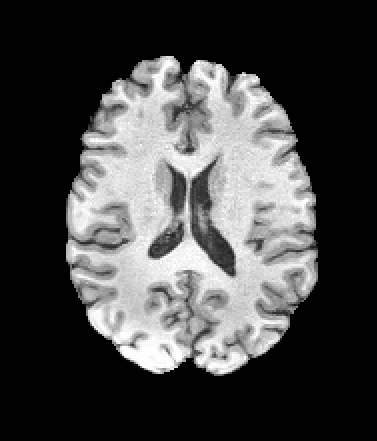

A trained MetaVoxel model can be unconditionally sampled by drawing Gaussian or categorical noise for each variable at timestep , and iteratively apply the denoising network until reaching . Unlike conventional diffusion models that focus solely on image generation, MetaVoxel can generate coherent synthetic patient profiles from the joint distribution , as shown in Figure 2.

| Age: 64.0 | Age: 53.8 | Age: 70.9 | Age: 76.9 |

| Sex: Male | Sex: Female | Sex: Female | Sex: Male |

![]() |

| Age: 80.9 | Age: 77.7 | Age: 73.2 | Age: 84.6 |

| Sex: Male | Sex: Female | Sex: Female | Sex: Female |